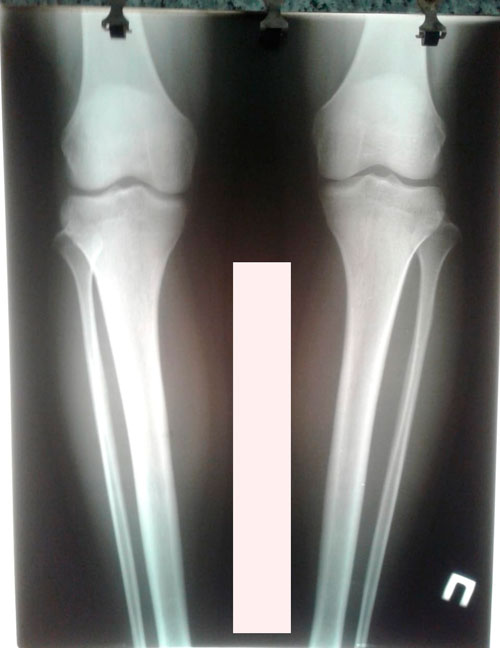

Дата операции-19.12.2018.

Дата снятия аппаратов - 18.02.2019г.

Срок сращения - 60 дней.